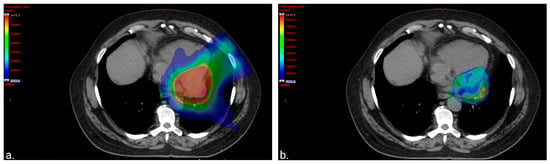

Figure 2.

Color wash images to visually represent the distribution of the radiation. (a). Color wash image of 20 gray (Gy) volume displaying sparing of the lung and anterior heart. The volume of the total lung receiving at least 20 Gy (total lung V20Gy) was equal to 10.6% (left lung V20Gy = 23.4% and right lung V20Gy = 0%). The heart mean dose was equal to 20 Gy with only 75 cubic centimeters (cc) of the treatment volume overlapping with the heart and 150 cc of the heart getting ≥30 Gy. (b). Color wash image of 50 Gy volume displaying sparing of the apex of the left ventricle from the prescription dose.